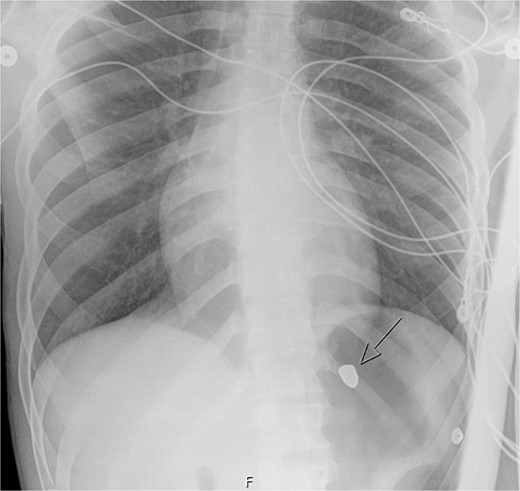

A 21-year-old male with a GSW to the left scapula presented to our Level 1 trauma center. He was stable but had flaccid paralysis and no rectal tone. A chest X-ray showed a bullet in the upper mediastinum (Fig. 1), prompting a computed tomography (CT) angiogram. The CT revealed a C6 cervical spine fracture, epidural hematoma, pneumomediastinum, and the bullet in the mediastinum at approximately the level of T3, but no hemorrhage (Fig. 2). Immediate upper endoscopy and bronchoscopy under general anesthesia were normal. He was extubated and monitored in the trauma ICU.

On hospital day (HD) 1, he developed ARDS and required intubation. He became hypotensive, raising concern for mediastinitis, but repeat imaging showed no new findings except that the bullet had migrated below the diaphragm (Fig. 3). Despite his septic appearance, his condition didn’t improve. He was diagnosed with severe AIDS (CD-4 count <100 cells/mm3) and multiple infections (hepatitis A, C, cytomegalovirus, toxoplasmosis, and multi-drug-resistant Pseudomonas pneumonia).